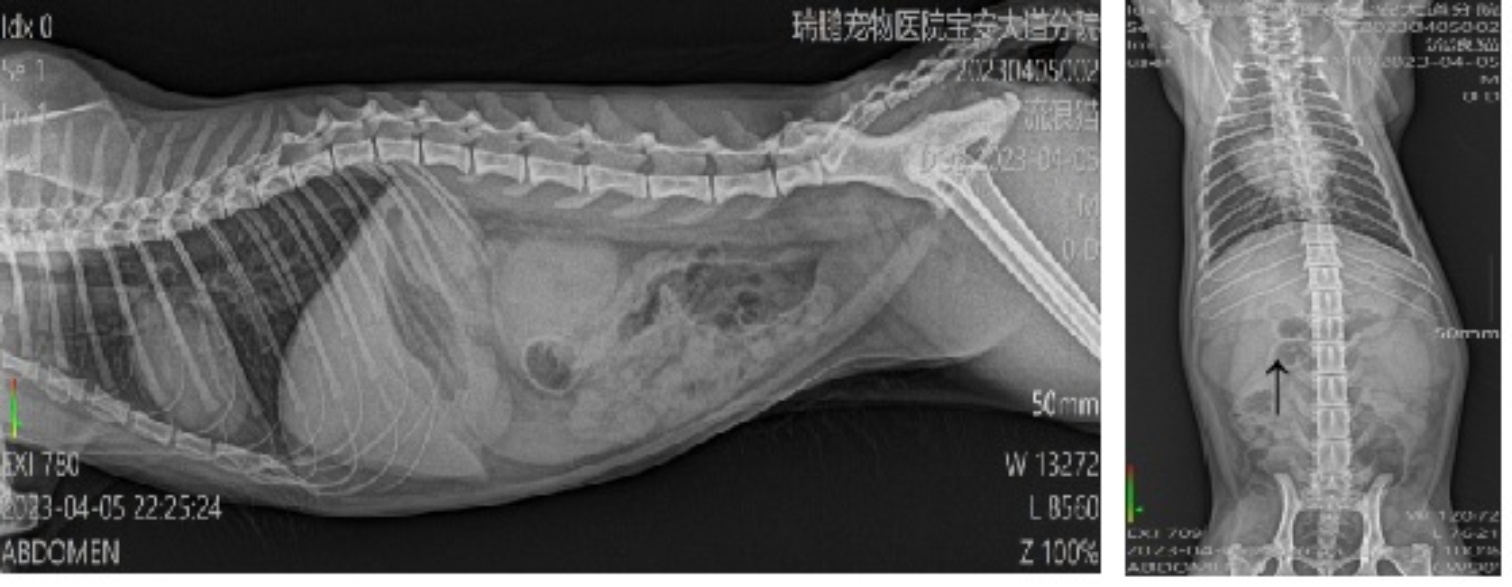

3.4. 腹部X光检查

腹部X线检查显示,肾区存在不明团块影,考虑可能与腹腔内积液或其他异常密度影有关。虽然该影像学表现不具有特异性,但提示腹腔内可能存在异常改变。初诊时患猫腹部触诊未见明显波动感,亦未表现出典型腹水体征,结合当时临床接诊条件,故未同步开展腹部超声检查。该检查缺失在一定程度上限制了对腹腔少量积液、肠系膜淋巴结及肝胆系统异常的进一步评估。同期SAA检测结果为32.8 mg/L,高于参考范围上限,提示患猫体内存在中度炎症反应。见图1表4

Figure 1. Radiographs of the cat: lateral view (left) and ventrodorsal view (right)

1. 该猫的X光图侧位(左)腹背位(右)